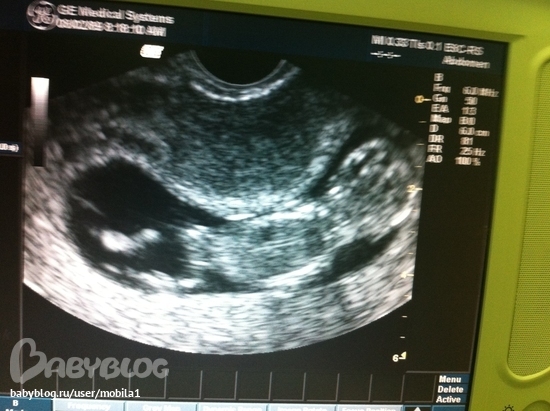

Сегодня ходила с мужем на узи. Это было здорово!!!! Он ворочался во все стороны, махал ручками и ножками. Мы не думали что они такие активные на таком маленьком сроке - 12 нед и 3 дня : ))))) Есть вероятность что будет мальчик, надеюсь так и будет!

Сердцебиение - 150 уд.

КТР - 58 мм

Диаметр желточного мешочка - 7 мм

БПР - 19 мм

ЛЗ - 23 мм

ТВП - 1,1 мм

ДБ - 7 мм

Если кто-то знает объясните что означает весь этот шифр? Знаю только что значит КТР.

БПР это бипариетальный размер головы, ТВП это толщина воротникового пространства, ДБ это длина бедренной кости. Что такое ЛЗ не знаю, все перекопала и не нашла. Все показатели у вас в норме!!! ПОЗДРАВЛЯЮ!!!!!!!!!!!!

Да здорово))) в 12 недель мне малышка ручкой махала )) папа проникся? Параметры я тебе попрбую завтра расшифровать! ))) милаха на фото)))